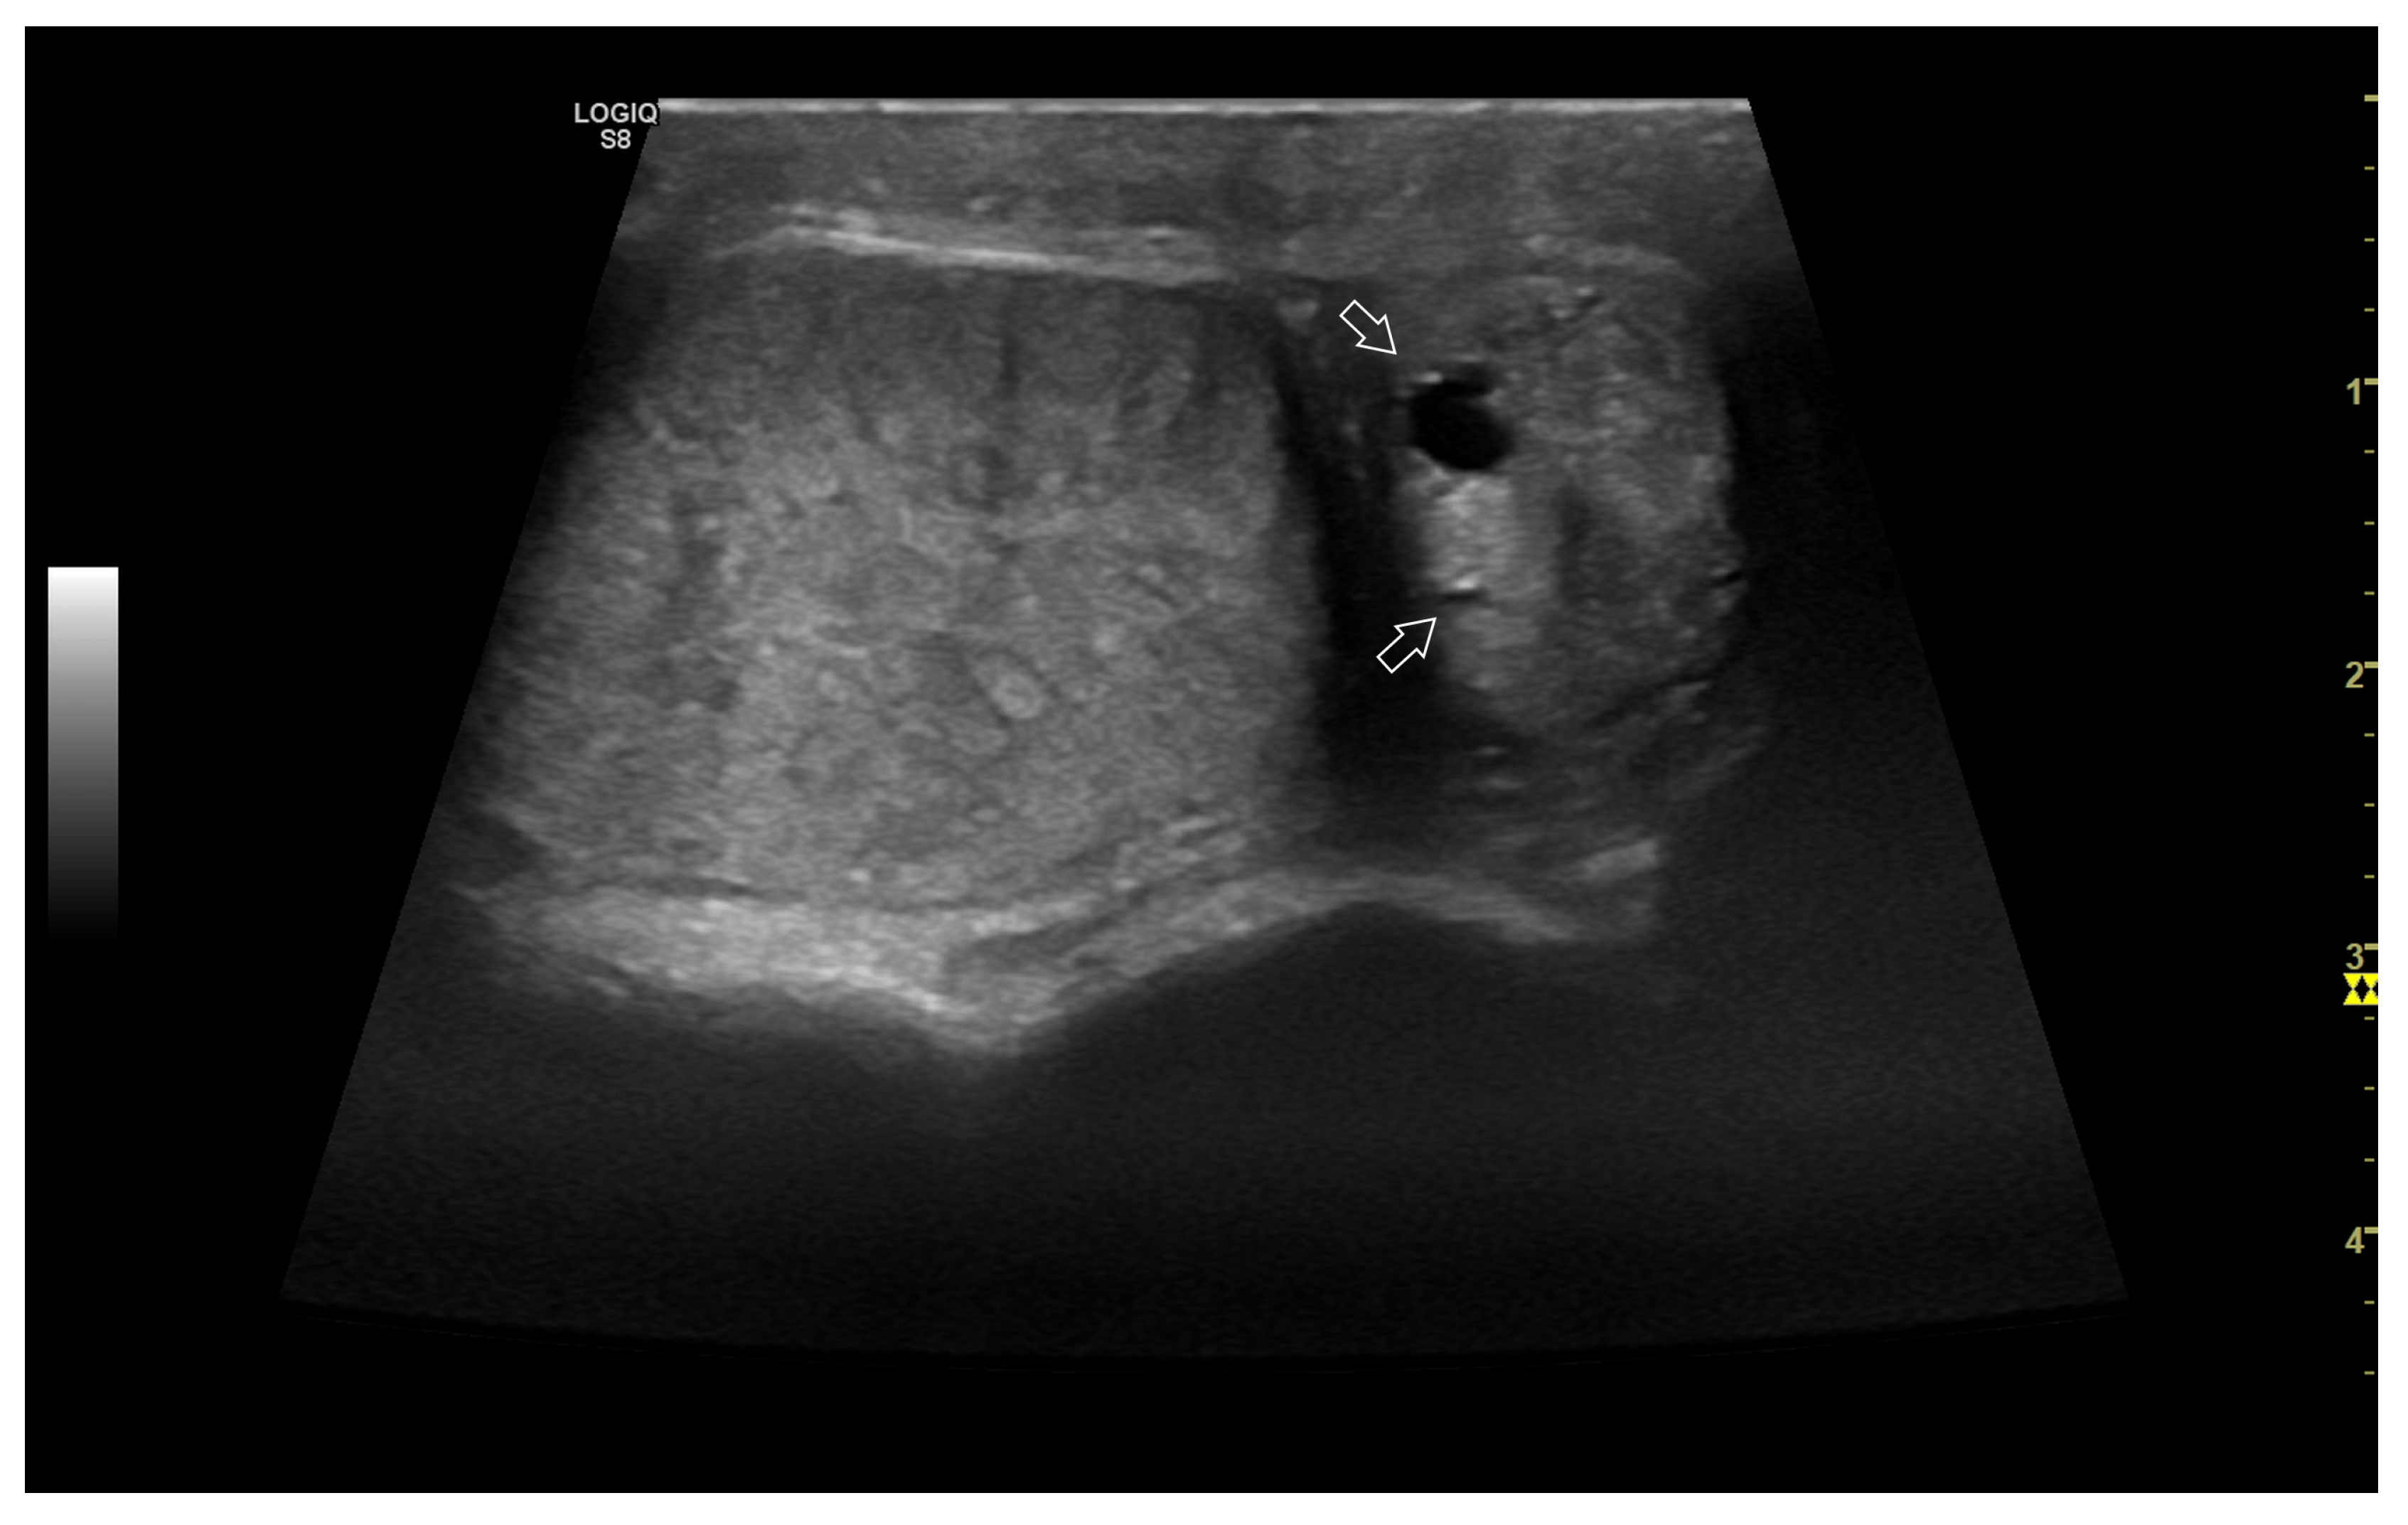

4. Colour Doppler and Power Doppler

4.2. Normal Findings

4.3. Relationship between Spectral Doppler Measurement and Dog’s Semen Quality

4.4. Abnormal Findings